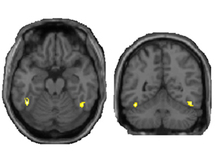

Nuevos datos demuestran que la visión es más compleja de lo que se creía. Fuente: Universidad de Duke.s previously thought. | Tobias Egner, Duke University.

Egner y sus colaboradores querían capturar todo el proceso casi al mismo tiempo que ocurría. Para ello, usaron una técnica conocida como exploración de resonancia magnética funcional (fMRI), que permite mostrar en imágenes las regiones cerebrales que ejecutan una tarea determinada.

En este caso, los investigadores se centraron en un área del cerebro conocida como área fusiforme para la cara (FFA por sus siglas en inglés), que se sabe está relacionada con la identificación de rostros.